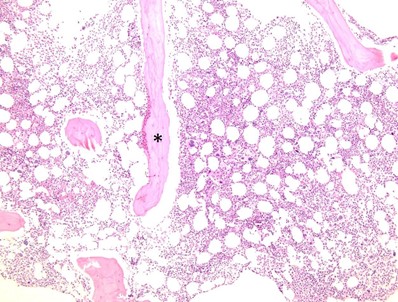

Figure 4. Bone core biopsy. Hematoxylin-eosin–stained section of the bone core biopsy (100×). Note the trabecular bone (*) with trilineage hematopoiesis including megakaryocytes, granulocytic precursors, and erythroid islands presented in 2D following formalin fixation and paraffin processing. View an interactive bone marrow core biopsy online.

The core biopsy is useful for assessing overall marrow cellularity, trilineage hematopoiesis, and marrow architecture. The prepared core biopsy slides can be used for immunohistochemical (IHC) investigations (phenotyping the cells using IHC stains), and an initial standard hematoxylin and eosin stain is done to assess baseline histology. After these initial assessments, immunostains often aim to assess architecture, fibrosis, lymphoid aggregates, myeloid lineage maturity, and other related potential pathologies. Since it is a two-dimensional specimen and reveals cells in cut section, it is not ideal for assessment of dysplasia (a marrow aspirate is preferred), but it is extremely useful in identifying possible reasons for a “dry tap” (a term for when liquid marrow cannot be aspirated during the bone marrow procedure), since the architecture can show fibrosis, sheets of cohesive plasma cells, or metastatic tumor which could result in a dry tap.